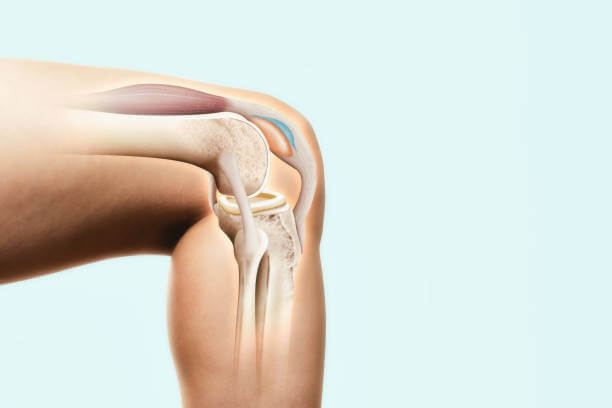

퇴행성 관절염

무릎을 장시간 사용하게 되면 연골이 약해져 벗겨질 수 있습니다. 그런 경우 관절이 매우 부드럽게 움직여야 하는데 거칠게 움직이면 삼출액이 차면서 고이게 됩니다. 경미한 퇴행성 관절염의 경우 활액의 양은 정상과 거의 같지만 증상이 심해지면 활액의 양이 3배 정도 늘어나 통증이 동반됩니다.

이 경우 물기를 제거하고 증상을 개선해도 거친 표면 자체가 해결되지 않으면 걸을 때마다 자극이 발생하여 다시 물이 차게 됩니다.

외상성 질환

반월판 손상, 전방십자인대 파열, 인대손상, 골절 등이 발생할 때 연골이 손상되면 염증으로 인해 활액이 과도하게 분비됩니다. 관절 연골 골절이 있으면 피가 나고 물이 차게 됩니다. 일반적으로 1~2개월 정도 지나면 저절로 좋아지지만 증상이 장기간 지속된다면 원인을 찾아 적극적으로 치료해야 합니다.